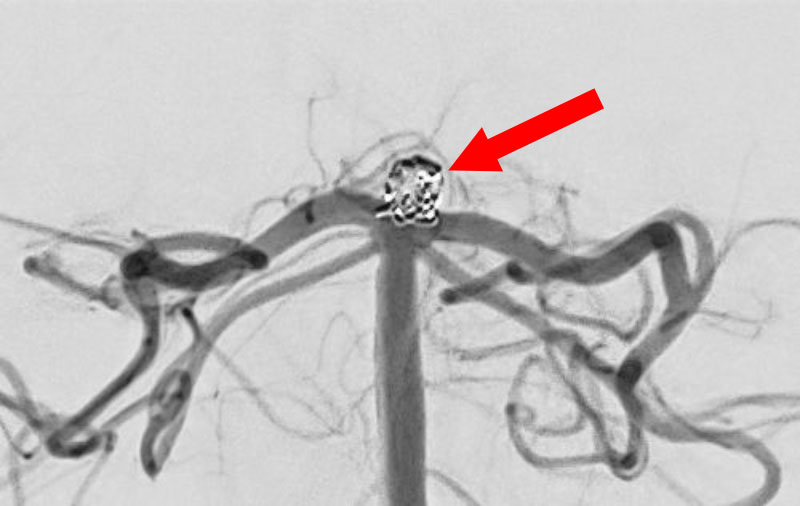

No.1627 手術中